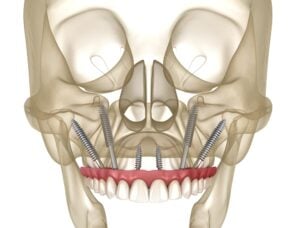

All-on-4® Dental Implants

Transform your smile with a fixed full-arch solution supported by just four dental implants

All-on-6 Dental Implants

A stable and durable option for patients who need additional implant support for long-term function.

Zygomatic & Pterygoid Implants

Advanced full-arch solutions for patients with severe bone loss or failed grafting, performed in-house by experienced clinicians.